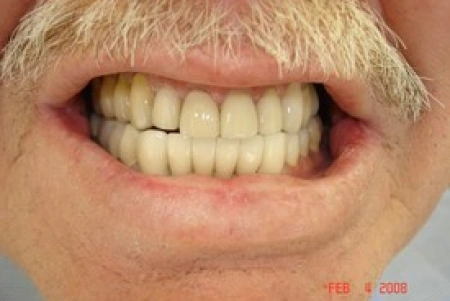

Before

After

Before: Patient needs Upper Arch Rehabilitation. Presents with Upper Anterior teeth that are stained, incisal edges (tooth edge) are worn down and chipped, and gumline recession is present.

After: Smile restored with placement of 8 Upper All Porcelain Crowns (Caps). Gumline and incisal edges are now uniform. Patient now has longer, better-shaped teeth to enhance the smile line and aid in chewing/biting function.